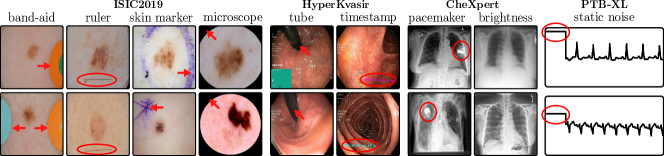

The considered datasets include ISIC2019 for melanoma detection [19, 70, 20], HyperKvasir for the identification of gastrointestinal abnormalities [10], CheXpert with chest radiographs [46], and the PTB-XL dataset [73] with 12-lead ECG (time series) data. All vision datasets contain real-world artifacts that DNNs may utilize as spurious correlation, i.e., features unrelated to the task, yet correlating with the target label. ISIC2019 is particularly known for various artifacts like colorful band-aids near benign lesions and rulers or skin markers beside malignant lesions [62, 3, 18, 59]. Moreover, HyperKvasir contains insertion tubes predominantly in samples without abnormal conditions, while CheXpert samples with cardiomegaly contain pacemakers in radiographs more frequently than in healthy patients [75]. In addition, we insert controlled artifacts into a subset of images from exactly one class per dataset. Specifically, we insert a microscope-like artifact into melanoma samples in ISIC2019. Moreover, following Dreyer et al. [28], we insert a timestamp into disease-samples from HyperKvasir, mimicking timestamps added by scanning devices. For CheXpert, we increase the brightness of radiographs with cardiomegaly, while for PTB-XL, we insert a static noise into the first second of one lead for samples with left ventricular hypertrophy (LVH). Inserting these artifacts into of samples from exactly one class creates spurious correlations for that class. Further dataset details are provided in Appendix A.4 and examples of the artifacts are shown in Fig. 5.

Considered Types of Data Artifacts

In this work, we focus on data artifacts caused by spurious correlations, i.e., concepts unrelated to the (medical) task, yet correlating with the target label due to biases in the dataset curation process. Whereas some artifacts are entirely irrelevant to the task, e.g., watermarks from medical devices, other artifacts can have a medical meaning but no causal impact on the predicted outcome, such as skin markers from dermatologists. We further distinguish between well-localized objects, such as band-aids or rulers, and non-localizable artifacts, e.g., slight color or brightness shifts caused by the usage of different medical scanners. Data artifacts can spatially overlap task-relevant information, such that masking out artifactual regions might remove important information. Moreover, spurious features can be conceptually entangled with valid features. For example, in melanoma detection, model representations for specific color patterns indicative of lesions may be entangled with natural variations in skin tone.